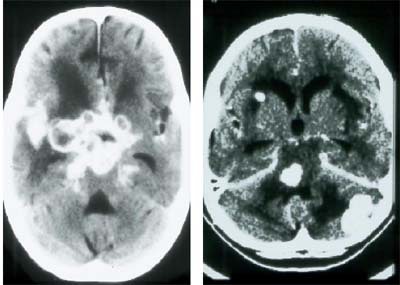

![]() |

| Infección por toxoplasmosis del cerebro de un paciente VIH positivo. Imágenes cortesía del Dr. Peter Corr. |